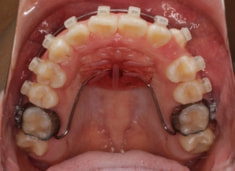

治療開始時